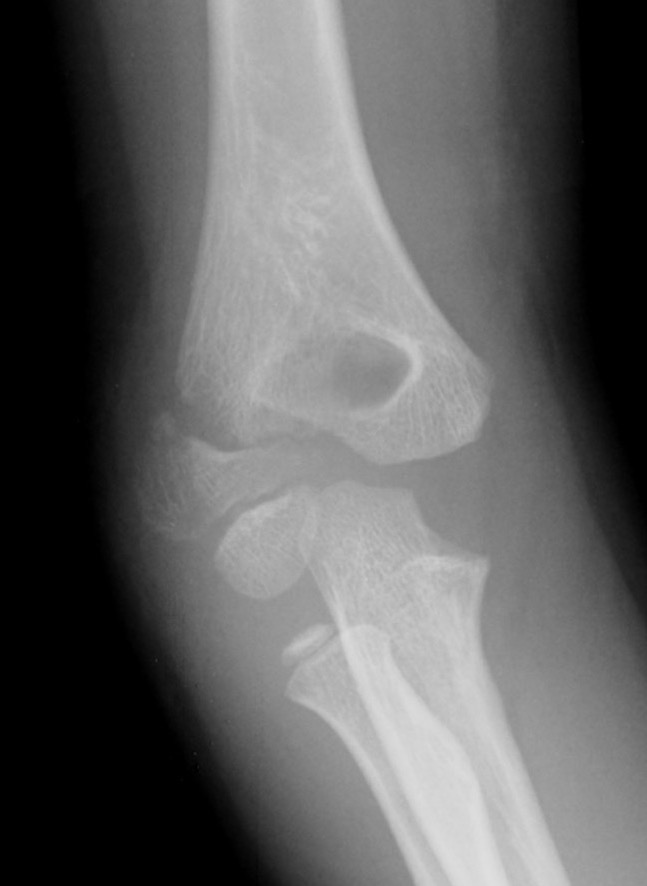

Lateral condyle fracture Image Lateral Condyle Arm Lateral condyle fractures are the second most common fracture in the pediatric elbow and are characterized by a higher risk of. Lateral humeral condyle fractures are the second most commonly encountered elbow fractures after the supracondylar type in the pediatric age group. Lateral condyle fractures of the elbow are the second most common paediatric elbow fracture after supracondylar fractures. The. Lateral Condyle Arm.

Lateral Condyle Arm . Lateral condyle fractures are the second most common elbow fracture after the supracondylar humerus fracture in children. Identifies fracture fragment as origin of common extensor tendon. Lateral humeral condyle fractures are the second most commonly encountered elbow fractures after the supracondylar type in the pediatric age group. Identify and mark out the lateral condyle. What is a lateral condyle fracture of the distal humerus? Operative management is essential for all patients with displaced fractures and for those demonstrating joint instability or the potential for delayed joint instability. The humerus is the long bone of the upper arm extending from the elbow to the. Lateral condyle fractures are the second most common fracture in the pediatric elbow and are characterized by a higher risk of. Lateral condyle fractures of the elbow are the second most common paediatric elbow fracture after supracondylar fractures.